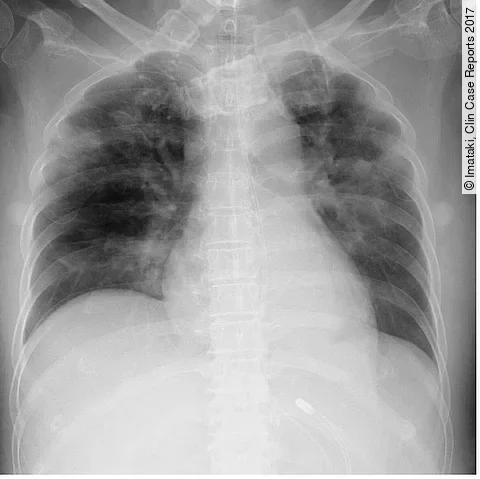

Röntgen-Thorax der Patientin mit Leukämie

Imataki, Clin Case Reports 2017

Nach der Knochenmarktransplantation aufgrund einer Leukämie kommt es bei der Patientin zu Komplikationen. Neben einer Enzephalitis ist auch die Lunge betroffen.